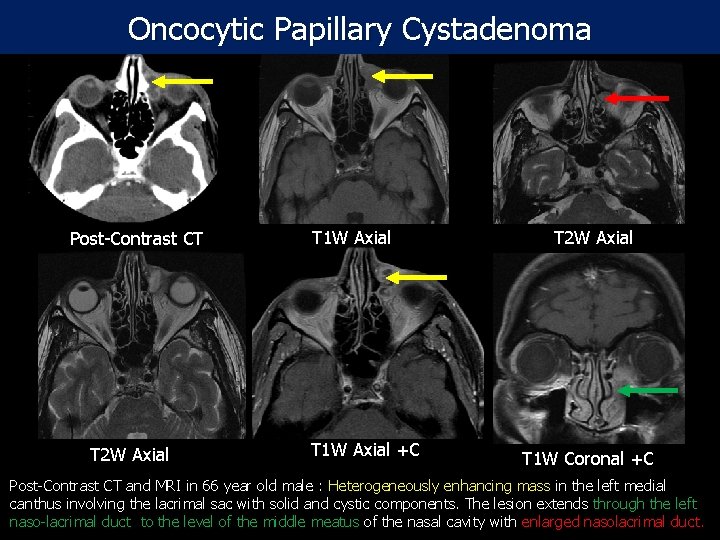

Oncocytic Papillary Cystadenoma Post-Contrast CT T 2 W Axial T 1 W Axial +C T 2 W Axial T 1 W Coronal +C Post-Contrast CT and MRI in 66 year old male : Heterogeneously enhancing mass in the left medial canthus involving the lacrimal sac with solid and cystic components. The lesion extends through the left naso-lacrimal duct to the level of the middle meatus of the nasal cavity with enlarged nasolacrimal duct.